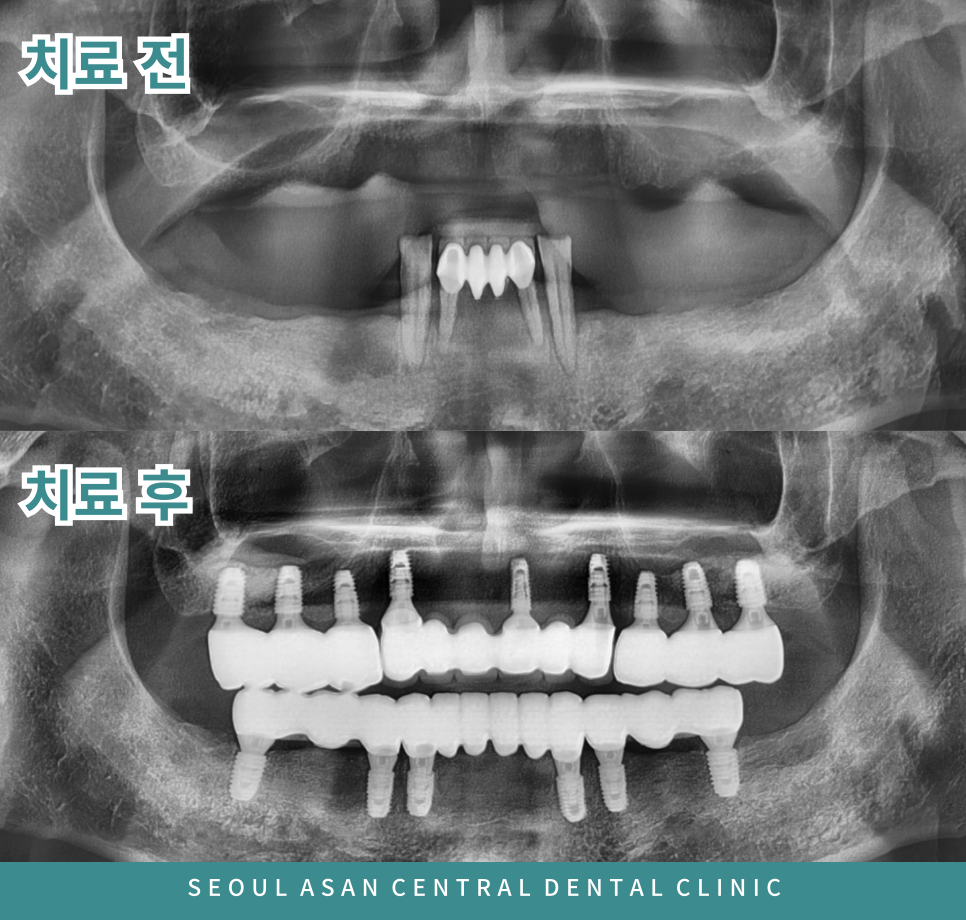

성남치과에서는 정밀한 검사를 위해 파노라마 사진을 촬영하여

이를 통해 잇몸뼈가 소실되어 있는지 확인을 합니다.

위 파노라마 사진처럼 위턱의 양측 어금니 부위는 상악동이 많이 내려와 있으면

상악동 거상술을 동반한 임플란트 식립이 필요할 수 있습니다.

임플란트 식립 이후 임플란트와 잇몸뼈가

단단하게 결합될 때까지 충분히 기다린 후

안정적인 상태가 되었을 때

위턱과 아래턱의 교합관계를 고려하여

보철물 치료로 마무리 되어야 합니다.